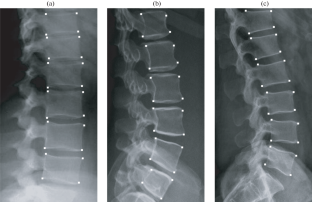

A method is proposed that allows one to determine the optimal values of the parameters of singular point detectors \(\mathbf{p}\) from the local characteristics of the image \({\mu}\). The method is based on searching for the extremum of the analytical dependence \(\delta=P(\mathbf{p},{\mu})\), where \(\delta\) is the detector efficiency criterion defined as the weighted sum of the type I error and type II error. The dependence \(P(\mathbf{p},{\mu})\) interpolates the set \(\delta(\mathbf{p}_{i},{\mu}_{j})\) obtained from a sample from a set of images of the same type. An experiment was performed with 40 radiographs of the lower part of the human spine, which were processed by the Harris–Stephens detector and SUSAN detector. It is found that when choosing the adjustable parameters of the detector using the proposed method, the \(\delta\) criterion turned out to be significantly lower than for the values of these parameters at the boundaries of the recommended intervals.